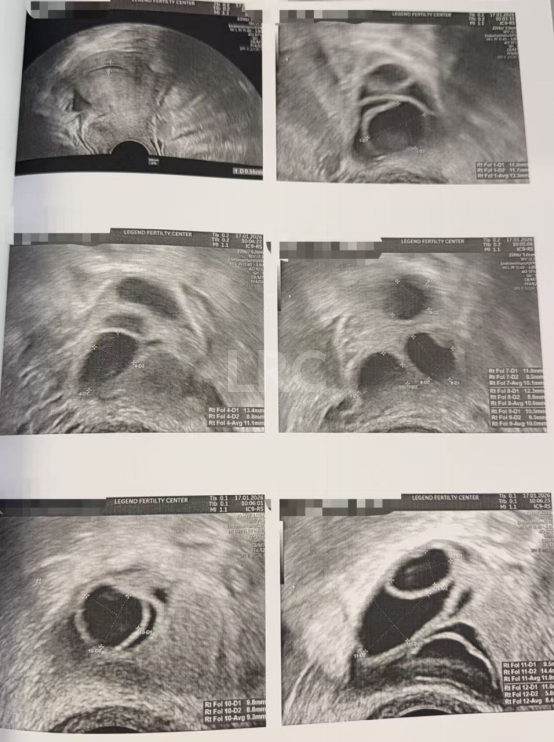

月经第二天 促排第一天

阴超检查:基础卵泡 16 颗

- 右侧卵泡 8 颗 (8,6,5,5,5,4,4,4mm)

- 左侧卵泡 8 颗 (6,6,6,5,5,5,5mm)

促排第四天

阴超检查(只数能用卵子):

- 右侧卵泡 8 颗 (10,9,9,8,7,7,7mm)

- 左侧卵泡 8 颗 (12,11,10,9,9,9,8,8mm)

子宫内膜厚度:6.4mm

促排第六天

阴超检查:

- 右侧卵泡 9 颗 (12,10,9,9,9,8,8,7,7mm)

- 左侧卵泡 9 颗 (13,11,11,11,10,10,9,6,6mm)

子宫内膜厚度:5.5mm

促排第九天

- 右侧卵泡 9 颗 (17,17,16,16,15,15,13,12,12mm)

- 左侧卵泡 10 颗 (19,17,16,16,15,15,14,14,13,12mm)

子宫内膜厚度:7.0mm

促排第十天

- 右侧卵泡 9 颗 (20,18,18,18,18,17,17,15,14mm)

- 左侧卵泡 10 颗 (21,20,20,20,20,18,17,13,12,12mm)

子宫内膜厚度:7.9mm